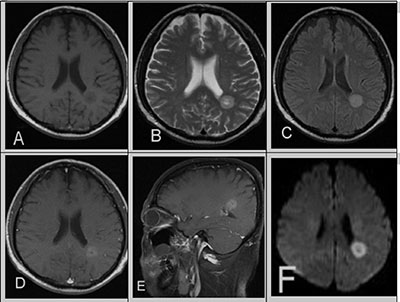

Figure 1: A 39-year-old male with a 10-year history of CML in relapse presents with headaches. (A) Unenhanced T1WI revealed a well-defined, heterogeneous brain parenchyma mass with mild hypointensity. (B) T2WI and (C) FLAIR showed hyperintensity, post-contrast. (D, E) T1WI showed mild hyperintensity and cystic changes. (F) DWI showed evidence of restricted diffusion in the corresponding area. There was no surrounding vasogenic edema or mass effect.